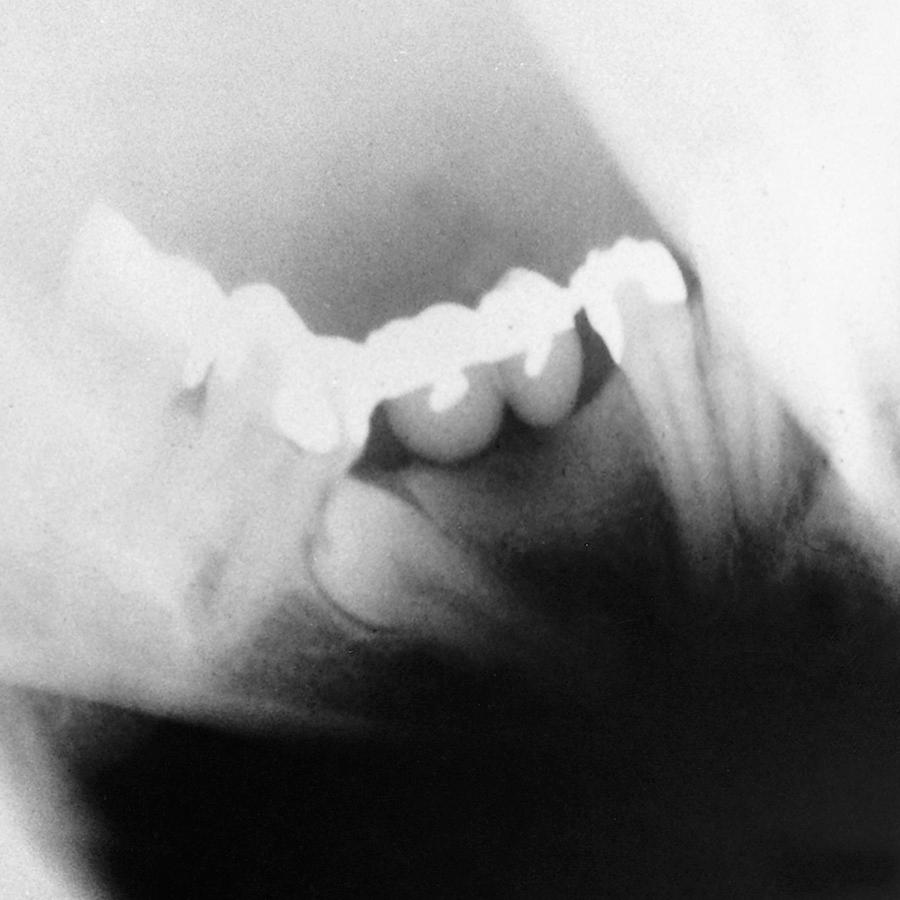

Erupted teeth adjacent to impacted teeth are predisposed to periodontal disease ( Figs. 10.1 and 10.2 ). The mere presence of an impacted mandibular third molar decreases the amount of bone on the distal aspect of an adjacent second molar. Because the most difficult tooth surface to keep clean is the distal aspect of the last tooth in the arch, patients commonly have gingival inflammation with apical migration of the gingival attachment on the distal aspect of the second molar. With even minor gingivitis, the causative bacteria gain access to a large portion of the root surface, which results in the early formation of periodontitis. Patients with impacted mandibular third molars often have deep periodontal pockets on the distal aspect of the second molars, even though they have normal sulcular depth in the remainder of the mouth.

Fig. 10.1, Radiograph of a mandibular third molar impacted against a second molar with bone loss resulting from the presence of a third molar.

Fig. 10.2, Radiographs showing variations of a mandibular third molar impacted against a second molar with severe bone loss resulting from periodontal disease and a third molar.